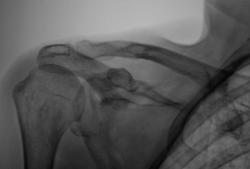

Какая-то она "дырявая". Может, череп снять, посмотреть, насколько это системно? На миелому не похоже?

У меня впечатление, что она "погрызена", мысли больше в сторону "опухолевого роста", но уверенности нет. Подожду, что скажут коллеги.